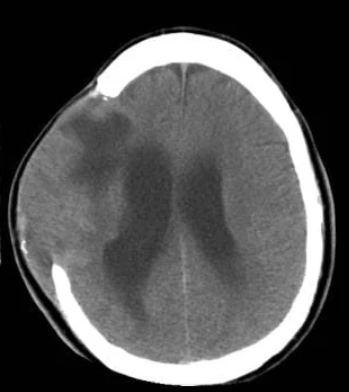

4 complications of skull fractures

epidural hematoma

causes rapid neuro decline

subdural hematoma

bleed after head injury

causes ⬆ICP→ HA, slurred speech

cerebral edema

⬇blood flow to brain

⬆ICP

brain herniation

brain tissue shifts d/t high ICP (life threatening!!)

Cushings

loss of blinking & gag reflex

pupils dont react to light